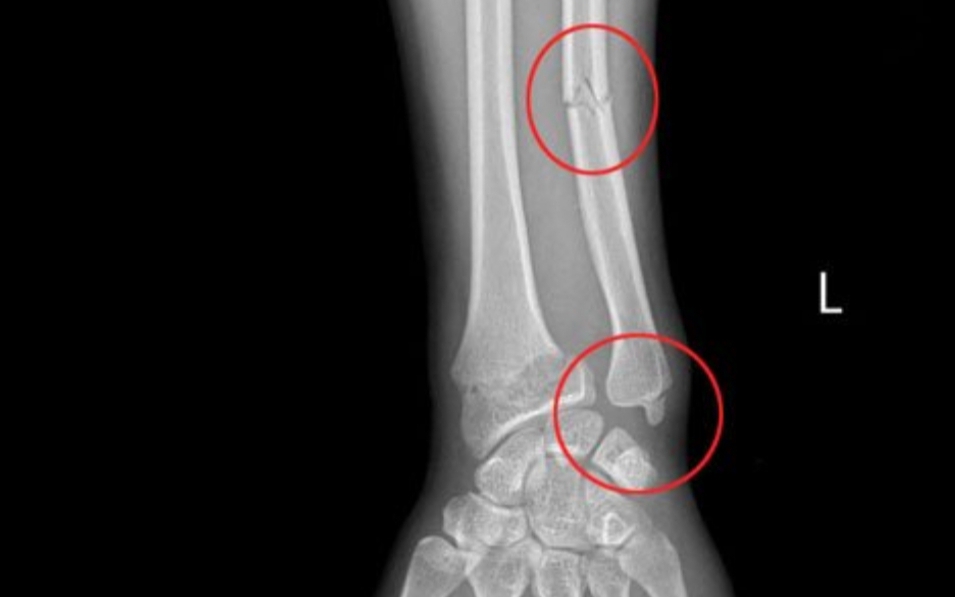

Đáng chú ý, bệnh nhân đến bệnh viện sau 15 ngày kể từ khi xảy ra chấn thương. Qua thăm khám kỹ lưỡng và chẩn đoán hình ảnh X-quang, các bác sĩ xác định đây là ca gãy cổ xương bàn tay số V điển hình.

Theo các bác sĩ gãy cổ xương bàn tay số V là loại tổn thương thường gặp sau một cú đấm không đúng kỹ thuật vào vật cứng hoặc các va chạm trực tiếp với cường độ mạnh.

Việc can thiệp phẫu thuật được chỉ định khi các chỉ số chấn thương vượt ngưỡng an toàn: diện gãy xoay trên 10 độ, xương bị ngắn trên 5mm hoặc gập góc trên 40 độ.